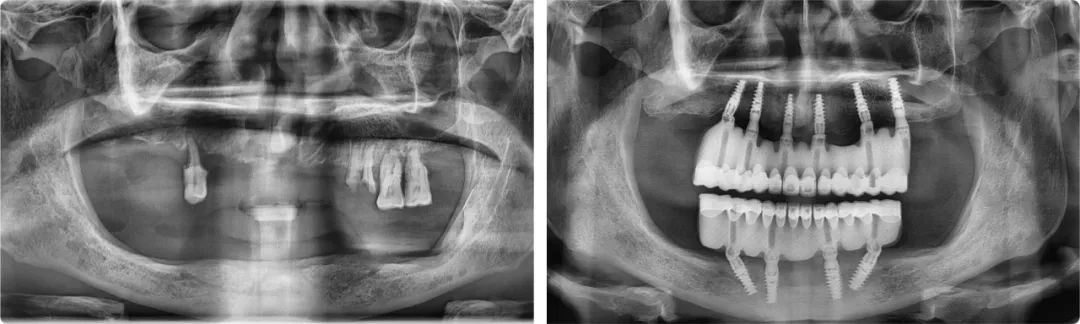

王旭東首例全口種植案例術前術后全景片

2019年12月31日,拔牙、植入10顆種植體、取模、戴牙(臨時修復體)、調整,當所有治療程序全部完成,時針已滑過零點。這次跨年手術是王旭東完成的第一例全口種植修復治療,也是陳醫生過得最開心的一個元旦。新的一年,他終于可以正常吃飯、說話,無所顧忌地大笑了。